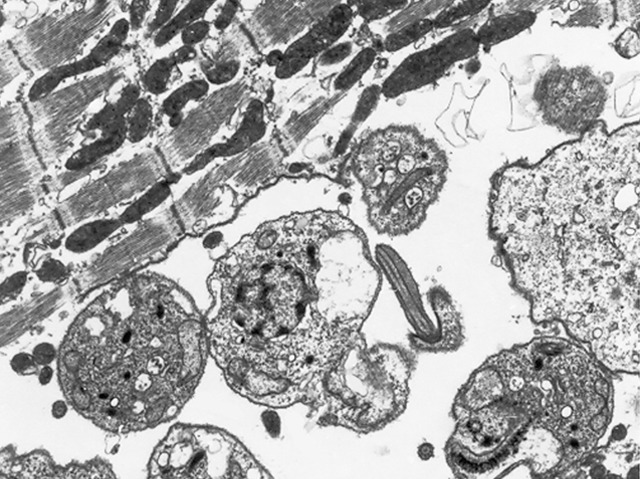

Chagas disease is one of the most common tropical illnesses in the world. It's caused by a tiny parasite called Trypanosoma cruzi which takes up residence in the heart and stomach muscles, and is shown here (the spheres) down a high-powered electron microscope infecting cells in the heart. The parasite can cause severe health problems for many years, and at the moment there’s no effective prevention against infection. That could be about to change thanks to the development of a potential new vaccine, which triggers the immune system to recognise and destroy Trypanosoma with a double punch. First comes an injection of DNA encoding two parasite-specific protein molecules, followed three weeks later by a booster jab containing the proteins themselves. In tests in mice, the vaccine seems to be having a positive effect, helping the immune system to keep parasite numbers under control and enabling it to fight off infection.